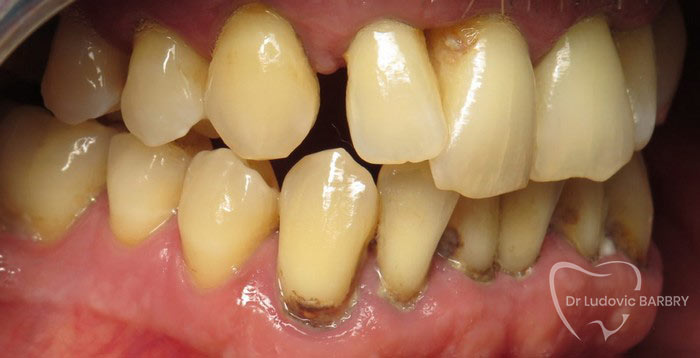

Parodontie Sévère

Grosse perte osseuse visible sur

la radio   on pourrait avec un stylet marquer en 2 couleurs le niveau osseux

actuel et normal

avant traitement